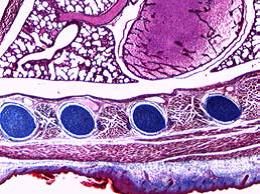

观察微小细节

光学品质卓越,呈现*精细的样本细节

-照明器、物镜、观察镜筒和目镜无缝结合,缔造出色的光学性能